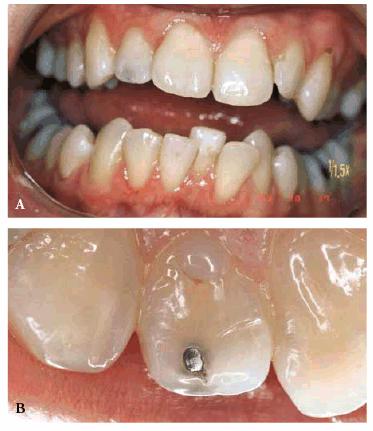

either on an individual tooth or on all teeth (Figures 16-1A, and 16-1B). There are many causes and

Figure 16-1A: An otherwise attractive smile is marred by discolored teeth.

Figure 16-1B: After tooth lightening, the smile is much more pleasing.